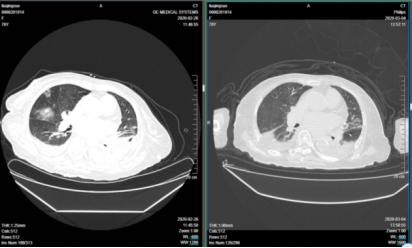

3月5日五诊:患者情况继续好转,精神可,静息状态无明显气促,活动后稍气促,鼻导管2L/min低流量吸氧,外周血氧饱和度99%,脱离氧气活动外周血氧饱和度亦无明显下降,咳痰量减少,胃纳可,大便通畅、每日1行,睡眠尚可。复查血常规示白细胞及中性粒细胞正常,淋巴细胞绝对值0.97×109/L。降钙素原0.17ng/ml。复查胸部CT提示“双肺病灶较前吸收,双侧胸腔积液”(图2-4-58)。舌淡红,苔薄白微腻,脉沉细。

图2-4-58 2020年2月26日与3月4日胸部CT